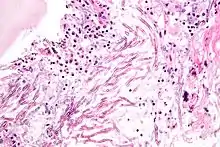

Cryptococcus neoformans puede causar una forma grave de meningitis y meningoencefalitis en pacientes con infección por VIH y SIDA . La mayoría de las especies de Cryptococcus viven en el suelo y no causan enfermedades en los seres humanos. Cryptococcus neoformans es el principal patógeno humano y animal. Este hongo no presenta ergosterol en su membrana. Se sabe que Cryptococcus laurentii y Cryptococcus albidus ocasionalmente causan enfermedad de moderada a grave en pacientes humanos con inmunidad comprometida. Cryptococcus gattii es endémico de las partes tropicales del continente de África y Australia y puede causar enfermedades en personas no inmunodeprimidas. [2]

Las células infectadas de C. neoformans suelen ser fagocitadas por macrófagos alveolares en el pulmón.[6] Las células invasoras de C. neoformans pueden morir por la liberación de moléculas oxidativas y nitrosativas por estos macrófagos. [7] Sin embargo, algunas células de C. neoformans pueden sobrevivir dentro de los macrófagos. La capacidad del patógeno para sobrevivir dentro de los macrófagos probablemente determina la latencia de la enfermedad, la diseminación y la resistencia a los agentes antifúngicos. Para sobrevivir en el entorno intracelular hostil del macrófago, una de las respuestas de C. neoformans es regular positivamente los genes empleados en las respuestas al estrés oxidativo .